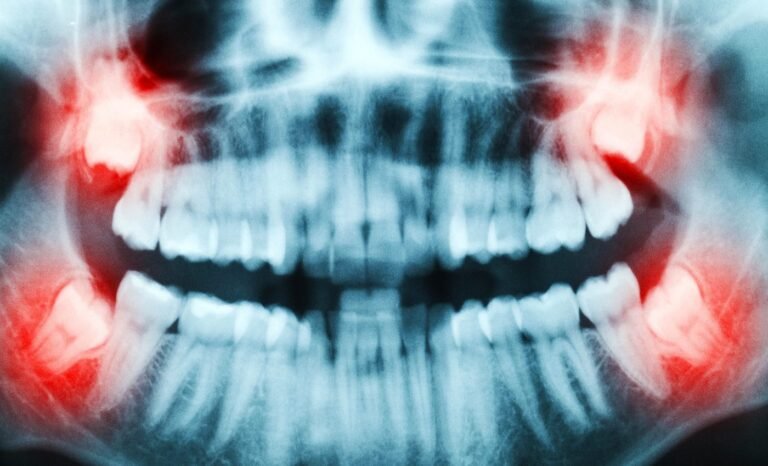

Milhões de pessoas extraem os dentes do siso todos os anos sem imaginar que estão descartando um verdadeiro tesouro biológico. Segundo pesquisa publicada na revista Stem Cell Research & Therapy, liderada pelo professor Gaskon Ibarretxe, da Universidade do País Basco, a polpa dentária desses dentes contém células-tronco poderosas, com capacidade de regenerar ossos, cartilagens e até tecido nervoso.